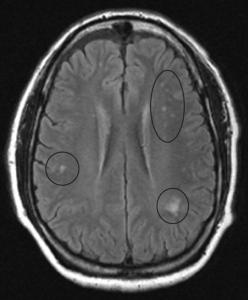

In this study, the researchers aimed to investigate the magnetic resonance imaging (MRI) and pathological characteristics of patients with LCL. Through bone marrow aspiration, they identified 14 cases of acute lymphoblastic leukemia (ALL), one case of chronic lymphoblastic leukemia, six cases of acute myeloid leukemia (AML), and one case of chronic myelomonocytic leukemia (CMML).

The clinical presentation among patients varied widely. Some experienced non-specific symptoms such as headache, vomiting, and limb convulsions, while others showed localized neurological deficits, including blurred vision and limb weakness. Using stereotactic intracranial lesion biopsy, the team found that 13 patients had CNS leukemia (CNSL), while the remaining nine had CNS secondary lesions related to leukemia treatment. These included five cases of CNS infection and four cases of neurodegenerative conditions.

The researchers also observed that imaging techniques such as cranial CT and MRI lacked sufficient specificity for identifying CNSL. Variability in CSF analysis and overlapping imaging features contributed to misdiagnoses, which in some reports may reach up to 75%. CNSL can be mistaken for a range of conditions, including meningitis, stroke, demyelinating disease, infection, or even Bálint syndrome.